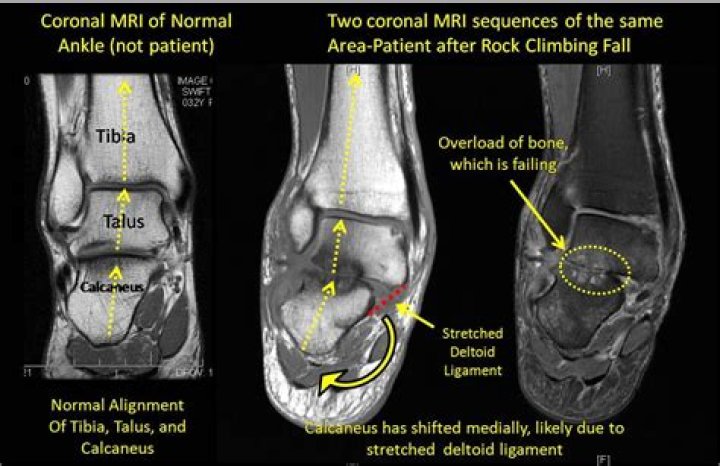

When using an MRI scan for ankle injury to assess for the severity of an ankle injury, magnetic fields and radiofrequency waves are used that provide high quality images of the tendons, cartilage and ligaments in the foot and ankle, that no other single imaging test is able to assess, thereby detecting stress fractures ...